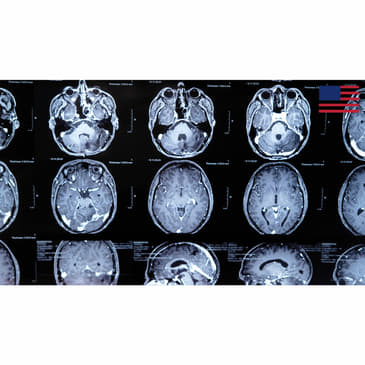

Thursday night's NFL game saw star quarterback Tua Tagovailoa suffer yet another severe concussion, possibly placing his career at risk. Dr. Pierre Kory talks about the science of concussions and whether professional sports has become too dangerous for its participants. Congressman Russ Fulcher talks about the details of Trump's latest campaign proposal to abolish taxes on overtime pay.